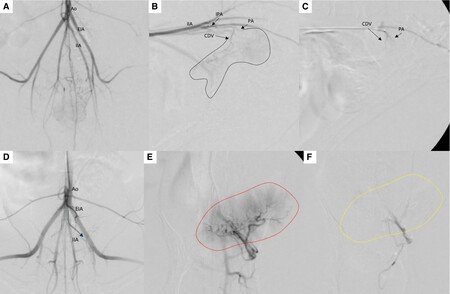

첫 번째 논문은 거대 방광 종양으로 지속적인 혈뇨와 빈혈을 보인 개 2마리에서 종양 색전술을 적용한 사례로 'Journal of Small Animal Practice(SCI)'에 게재됐다.

전통적으로 비뇨기 종양 색전술은 합병증 위험으로 전립선 종양에만 국한됐지만 본 증례는 종양으로 공급되는 혈관만을 초선택(superselective) 했고, 시간이 지나 재개통이 되는 색전 물질(gelatin sponge particle)을 이용해 효과를 극대화 하면서도 심각한 합병증이 발생하지 않도록 하였다.

시술 직후 혈뇨는 즉시 개선됐으며, 배뇨곤란 증상도 완화됐다. 또한 종양 크기는 50% 이상 감소했으며, 빈혈과 혈소판 감소증을 보였던 환자에서도 4주만에 혈액 수치가 정상화 되었다.